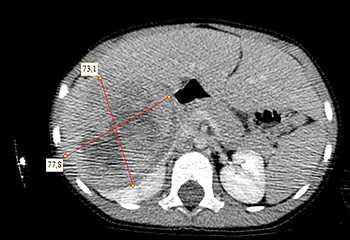

Ребенку проведена предоперационная химиотерапия. На 5-й неделе лечения КТ-контроль показал уменьшение опухоли в размерах до 90ґ80ґ100 мм (см. рис. 3).

Выполнена операция: лапаротомия, удаление опухоли правой почки с ее резекцией. Гистологическое заключение: классическая нефробластома, промежуточная группа риска (см. рис. 4).